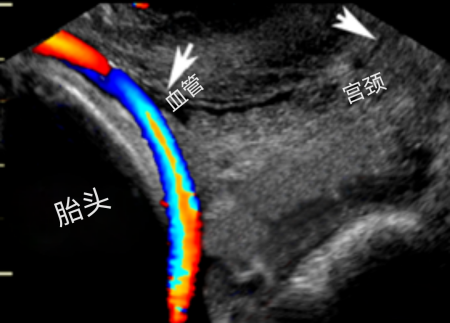

孕妈王某(化名)在中山市博爱医院(市妇幼保健院)进行产检时,中孕期超声检查显示帆状胎盘。为进一步评估,随即进行经阴道彩色多普勒超声检查,惊现胎儿血管横跨孕妈妈宫颈内口,这些暴露的血管犹如潜在的“定时炸弹”,对母婴安全构成重大威胁。

鉴于此,产科专家为孕妇精心定制产检路径及安全的分娩方案。待37周时胎膜早破,紧急剖宫产顺利诞下了一名健康宝宝。术中发现脐带附着胎膜,脐带附近血管附着胎膜插入胎盘,胎膜破口上方见一粗大血管,确诊为罕见的前置血管。

医生会用肚子上的探头(经腹)+ 更精准的阴道探头(经阴道)配合彩色多普勒超声,“双剑合璧”在最佳时间(孕18-26周)才能看得最清楚。B超看啥?就看宝宝“出生大门”(宫颈内口)上方或附近,有没有不该在那的“小水管”(血管)在噗噗跳动(血流信号)?有的话,基本就是它了!